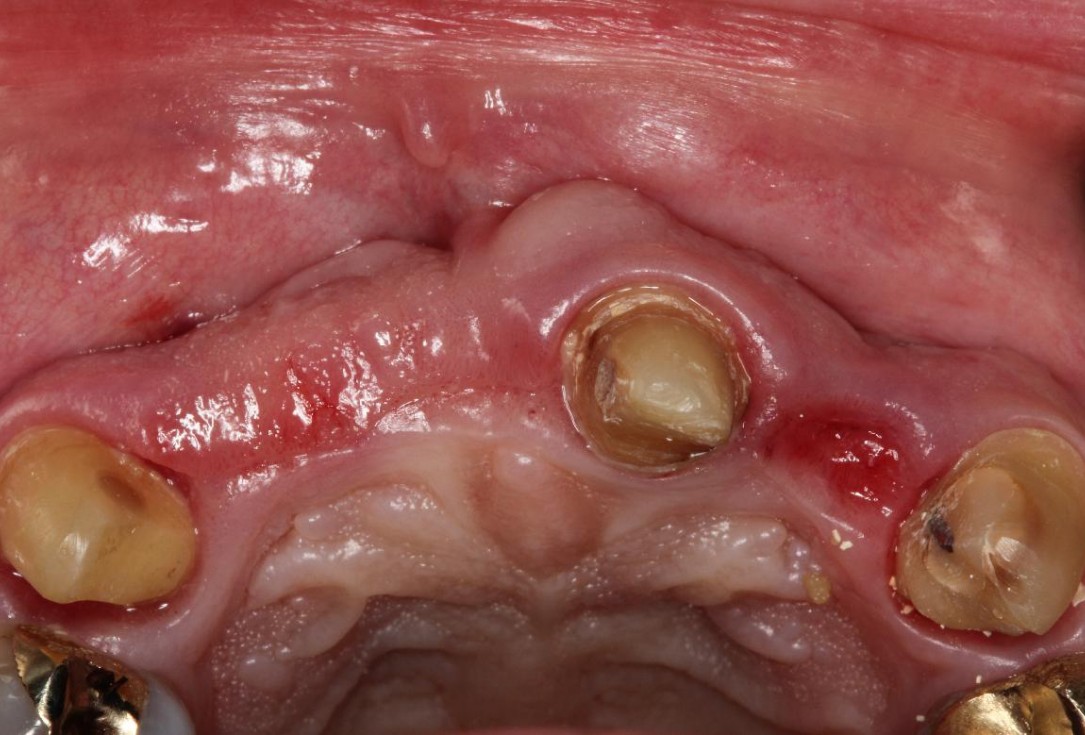

1/5 - Initial clinical situationPre-prosthetic soft tissue augmentation of the ridge contour with mucoderm®- Dr. F. Rathe